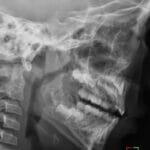

- Radiology Cases: Images with a to-the-point discussion highlighting the specific diagnostic criteria.

- Radiology Case of the Day Collection: Aunt-Minnie Board Cases for Rapid Review.

- Radiology Spotters: 700+ spot / “Aunt-Minnie” cases divided into sets of 10 each!